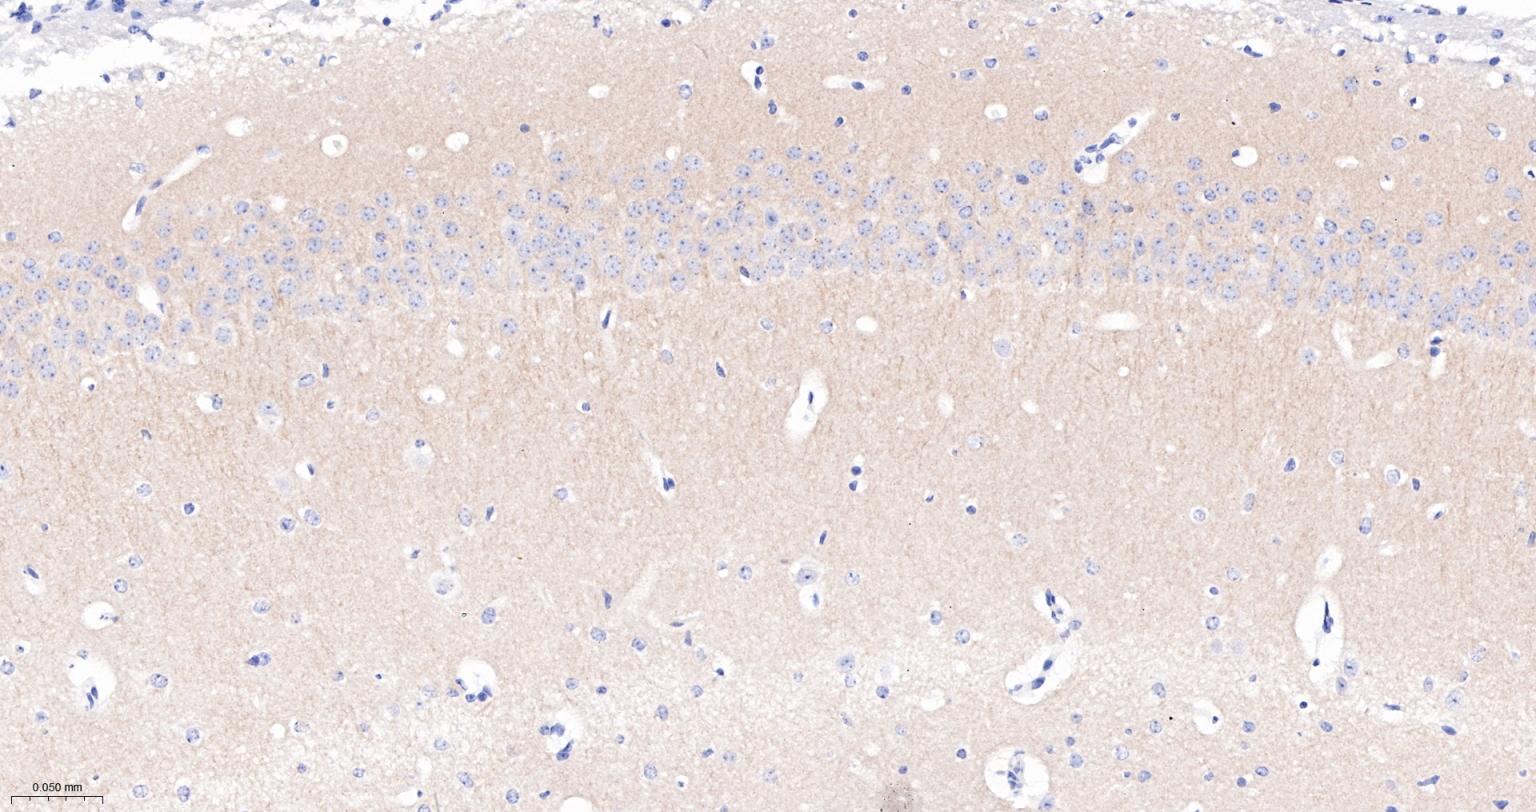

Paraformaldehyde-fixed, paraffin embedded Rat Cerebrum; Antigen retrieval by boiling in sodium citrate buffer (pH6.0) for 15 min; The section was incubated with PSD95 Monoclonal Antibody, Unconjugated (bsm-55665R) at 1:200 overnight at 4°C, followed by conjugation to the bs-0295G-HRP and DAB (C-0010) staining.

Paraformaldehyde-fixed, paraffin embedded Mouse Cerebrum; Antigen retrieval by boiling in sodium citrate buffer (pH6.0) for 15 min; The section was incubated with PSD95 Monoclonal Antibody, Unconjugated (bsm-55665R) at 1:200 overnight at 4°C, followed by conjugation to the bs-0295G-HRP and DAB (C-0010) staining.